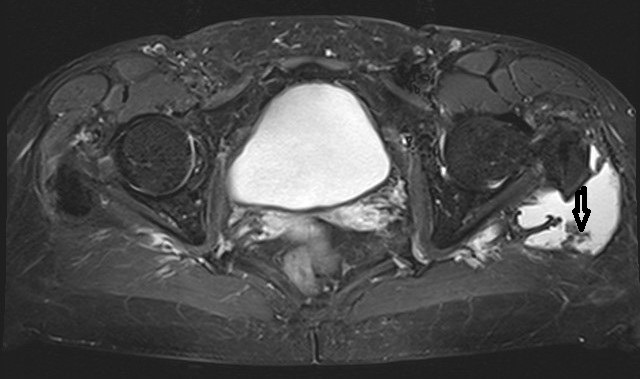

This is the first report on a localized pigmented villo-nodular synovitis (PVNS or TSGCT) occurring in the trochanteric bursa. Bursal involvement in PVNS is extremely rare. Most often PVNS occurs either as a localized or diffuse lesion in a major synovial joint, such as the knee, ankle joint or hip joint. In principle, all synovial structures can be involved. The case reported here is remarkable regarding the long period between the occurrence of the first symptoms and the final diagnosis as well as the age of the female patient (75 yrs). Therapeutically a complete resection was performed in order to avoid recurrence. More then three years later the patient did well and there has been no evidence of recurrence yet.